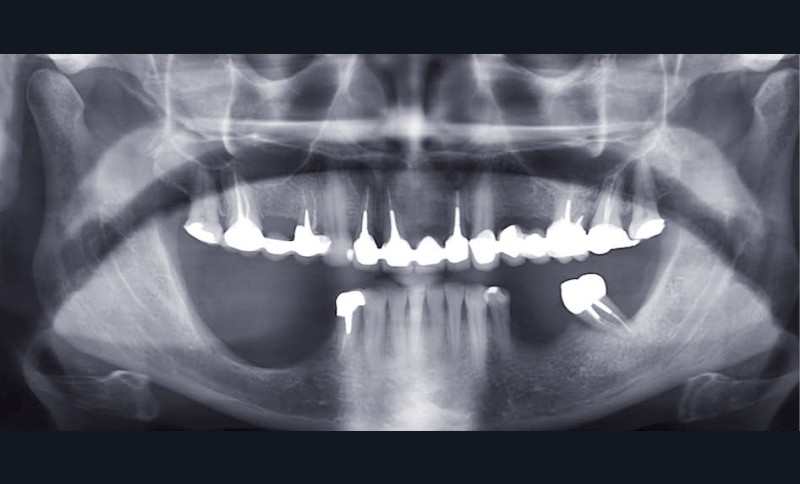

Examen radiographique